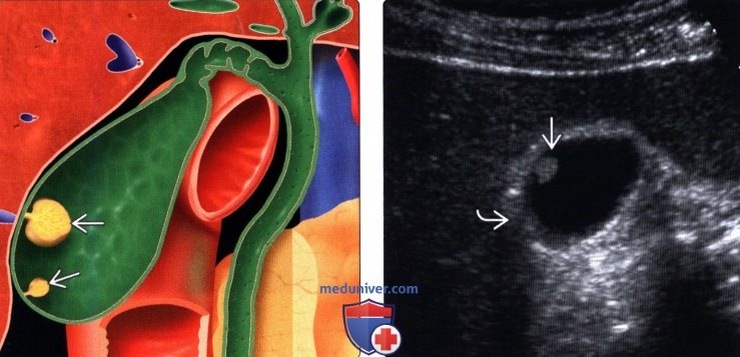

Представьте ваш желчный пузырь как небольшой мышечный мешочек, где хранится и концентрируется желчь. Полип — это доброкачественное образование, своеобразный «вырост» на его внутренней стенке. Он может быть разной формы: на тонкой ножке или на широком основании.

1. Псевдополипы (холестериновые). Это самые частые и добрые «соседи»! 🙌 Составляют до 80% всех случаев. На самом деле, это даже не истинные полипы, а отложения холестерина на стенке пузыря. Они выглядят как небольшие бляшки или «сосульки» и не превращаются в рак. Часто их находят у людей с нарушениями холестеринового обмена.

4. Полипы-призраки. Иногда за полипы на УЗИ принимают густую, замазкообразную желчь, которая прилипает к стенкам. При контрольном исследовании этот «полип» часто бесследно исчезает.